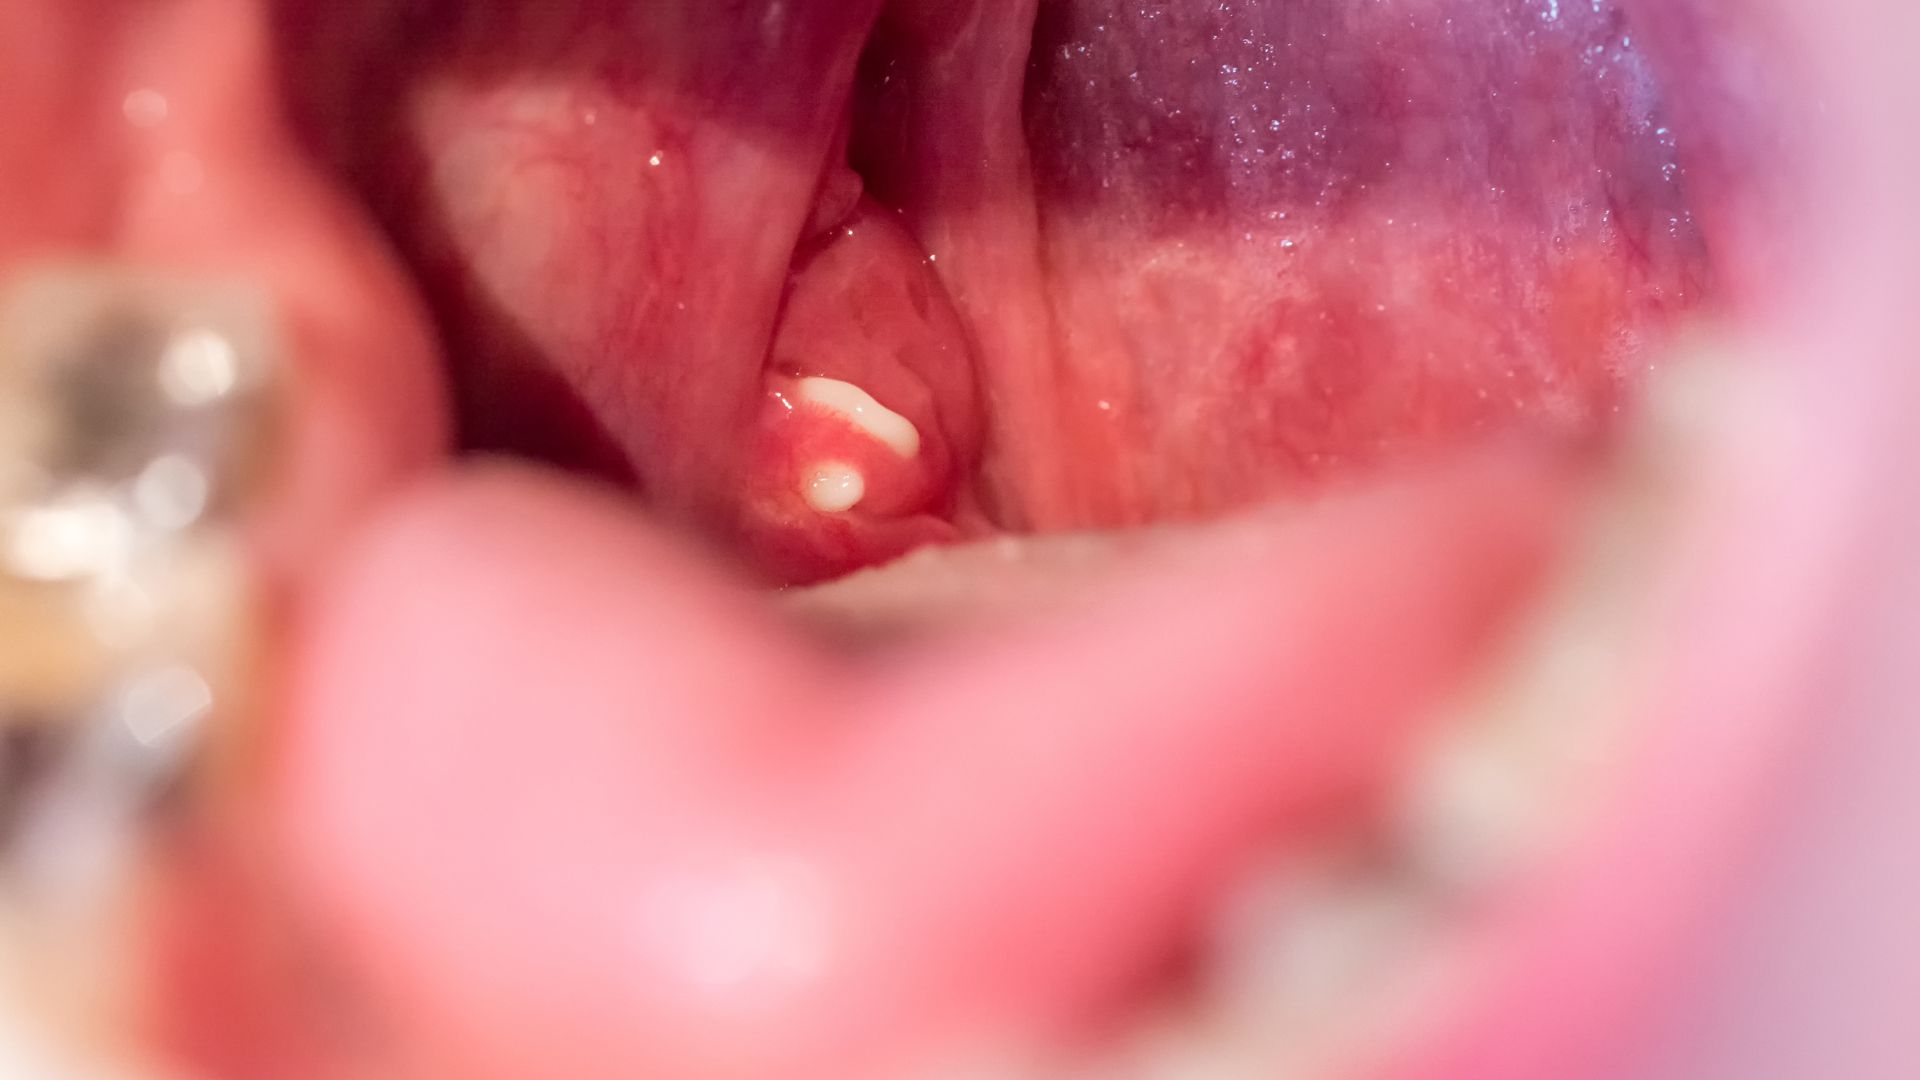

- Hình ảnh bình thường: Khi nội soi, niêm mạc vòm họng có màu hồng nhạt, bề mặt trơn láng, không xuất hiện khối u hay tổn thương bất thường.

Khối u có thể lành tính hoặc ác tính, song đều gây ra những phiền toái cho sức khỏe. U lành thường phát triển chậm, biểu hiện nhẹ nhàng như nghẹt mũi hoặc cảm giác vướng họng. U ác tính tiến triển nhanh, dễ xâm lấn sang hốc mũi, tai hoặc hạch cổ. Người bệnh có thể bị chảy máu mũi, ù tai, đau đầu kéo dài. Vì triệu chứng ban đầu mơ hồ, nhiều trường hợp chỉ phát hiện khi bệnh đã tiến triển. Do đó, nội soi kiểm tra định kỳ vùng mũi họng là phương pháp phát hiện sớm cần được ưu tiên.